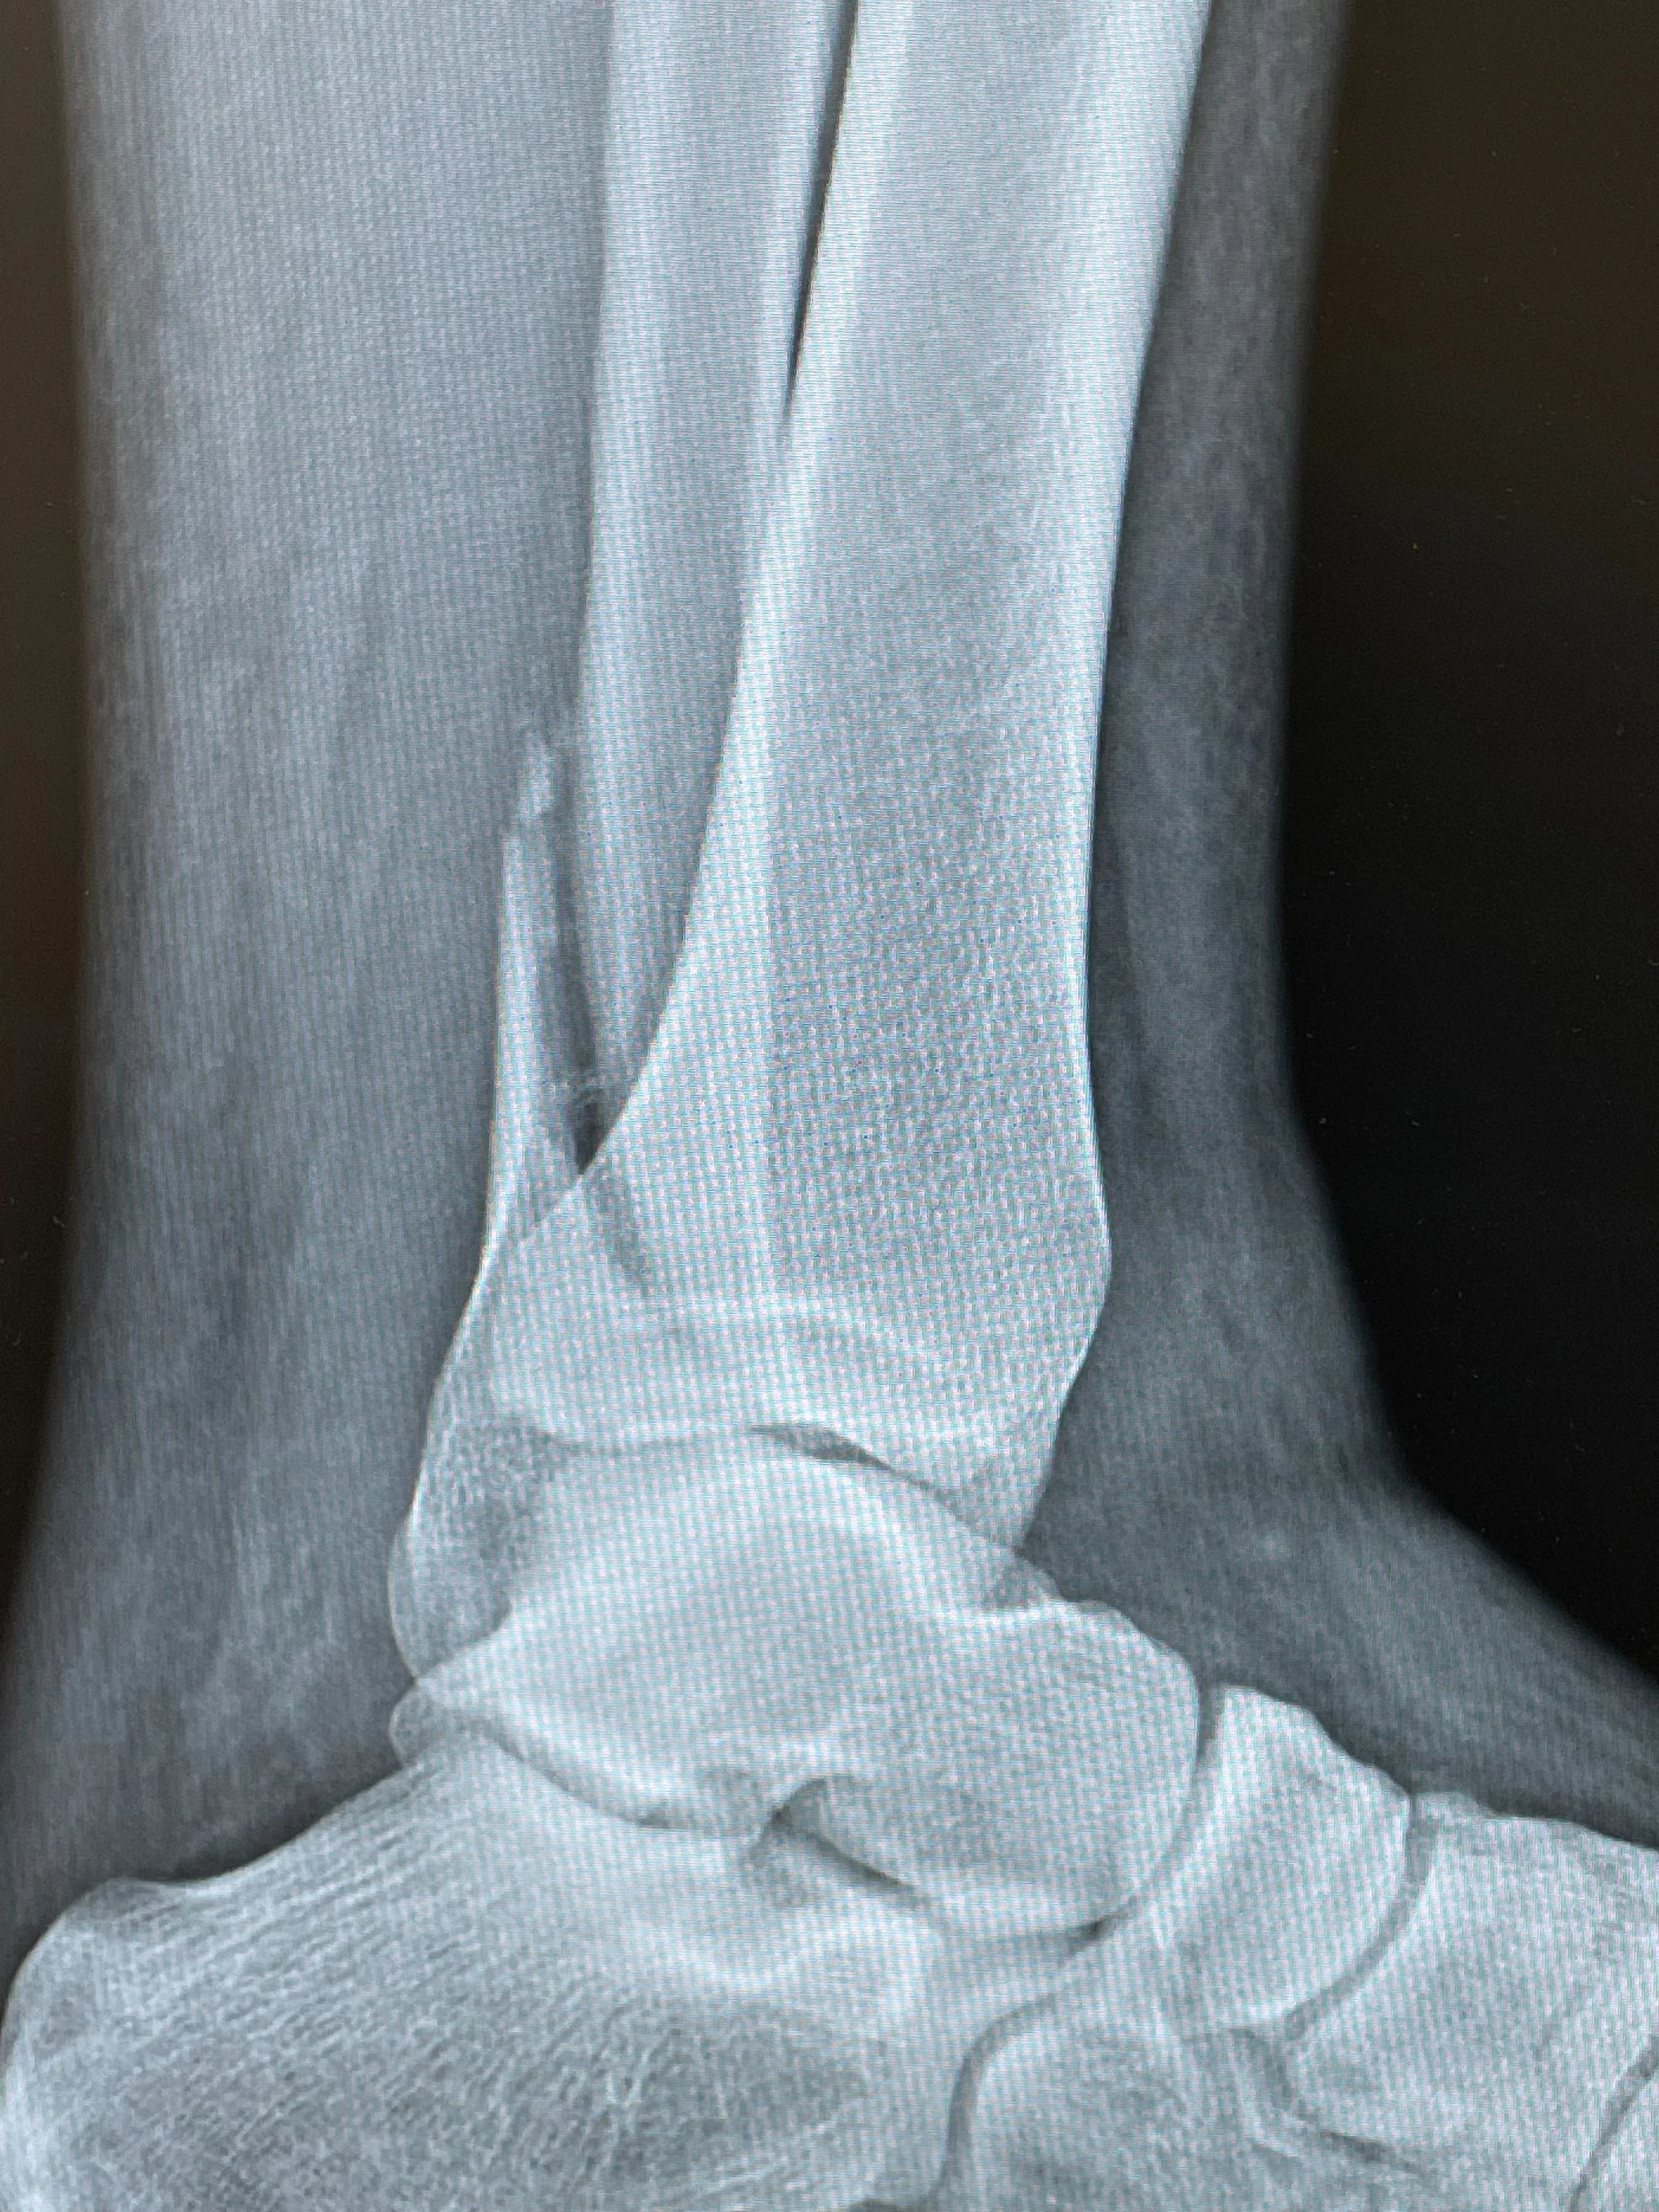

Ankle Fracture

The fibula only bears 15% of the body weight. Resultingly, when patients fracture the fibula often times they can still bear weight/ambulate on the leg, although very painful. Deviation of the fibula can cause biomechanical changes and misalignments which result in ankle instability and arthritis down the road. This injury is 3 days out and the displacement of the fracture now dictates open reduction, AKA, surgery. If proper medical consult was obtained immediately after the injury and non-weightbearing was initiated immediately it is possible surgery may have been avoided, depending on the fracture gap. Lesson to be learned……if/when you have a substantial injury to the foot/ankle, even if you can still ambulate and weight bear, get it checked out.